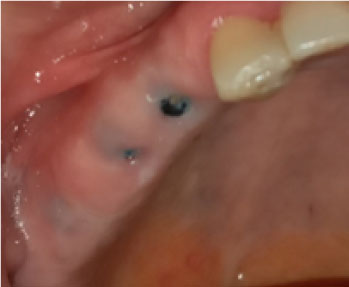

In terms of severity, Class I exposure was the most common with seven implants. Moreover, Class III was the least common with only one implant. The number of exposed maxillary and mandibular implants is presented in Figure 1. Also, Figures 2-6 show the exposure of maxillary premolar implants.

Figure 3. Class III exposure of a maxillary premolar implant.